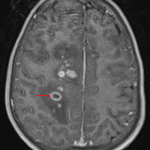

Indication: Headache, history of renal transplant

- Numerous hyperattenuating foci in the cerebral and cerebellar white matter bilaterally with associated vasogenic edema

MRI

- Numerous enhancing lesions in the bilateral cerebral and cerebellar hemispheres, the cerebellar vermis, and the medulla, many of which are periventricular in location and extend to the ependymal surface of the ventricles

- The majority of these lesions demonstrate solid enhancement, though a few demonstrate peripheral enhancement

- Variable corresponding restricted diffusion

- Corresponding vasogenic edema and mass effect without midline shift or evidence of herniation or hydrocephalus

Post-transplant lymphoproliferative disorder (PTLD)